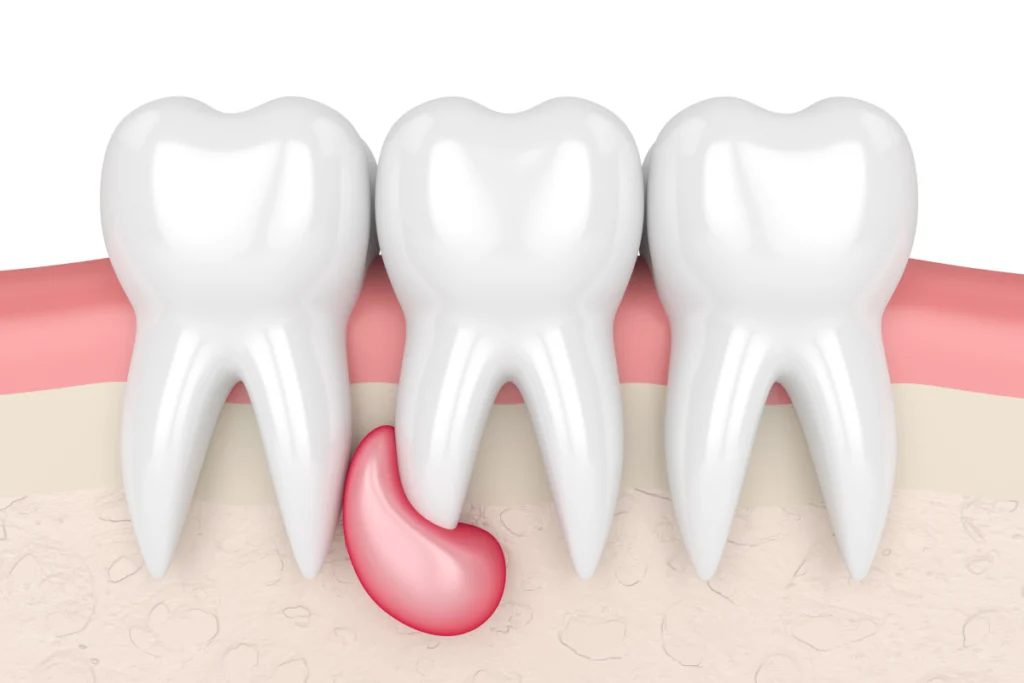

- Gonflement ou abcès : Un gonflement visible ou un abcès autour de la dent.

Un retraitement endodontique est nécessaire lorsque le traitement initial de canal n’a pas réussi à éliminer l’infection ou lorsque des complications surviennent. Cela peut être dû à une obturation incomplète des canaux ou à la présence de canaux non traités.

Les signes qui indiquent qu’un retraitement est nécessaire comprennent :

- Douleurs récurrentes après un traitement de canal

- Gonflement ou abcès persistants autour de la dent traitée

- Radiographies montrant une infection non traitée dans les canaux radiculaires